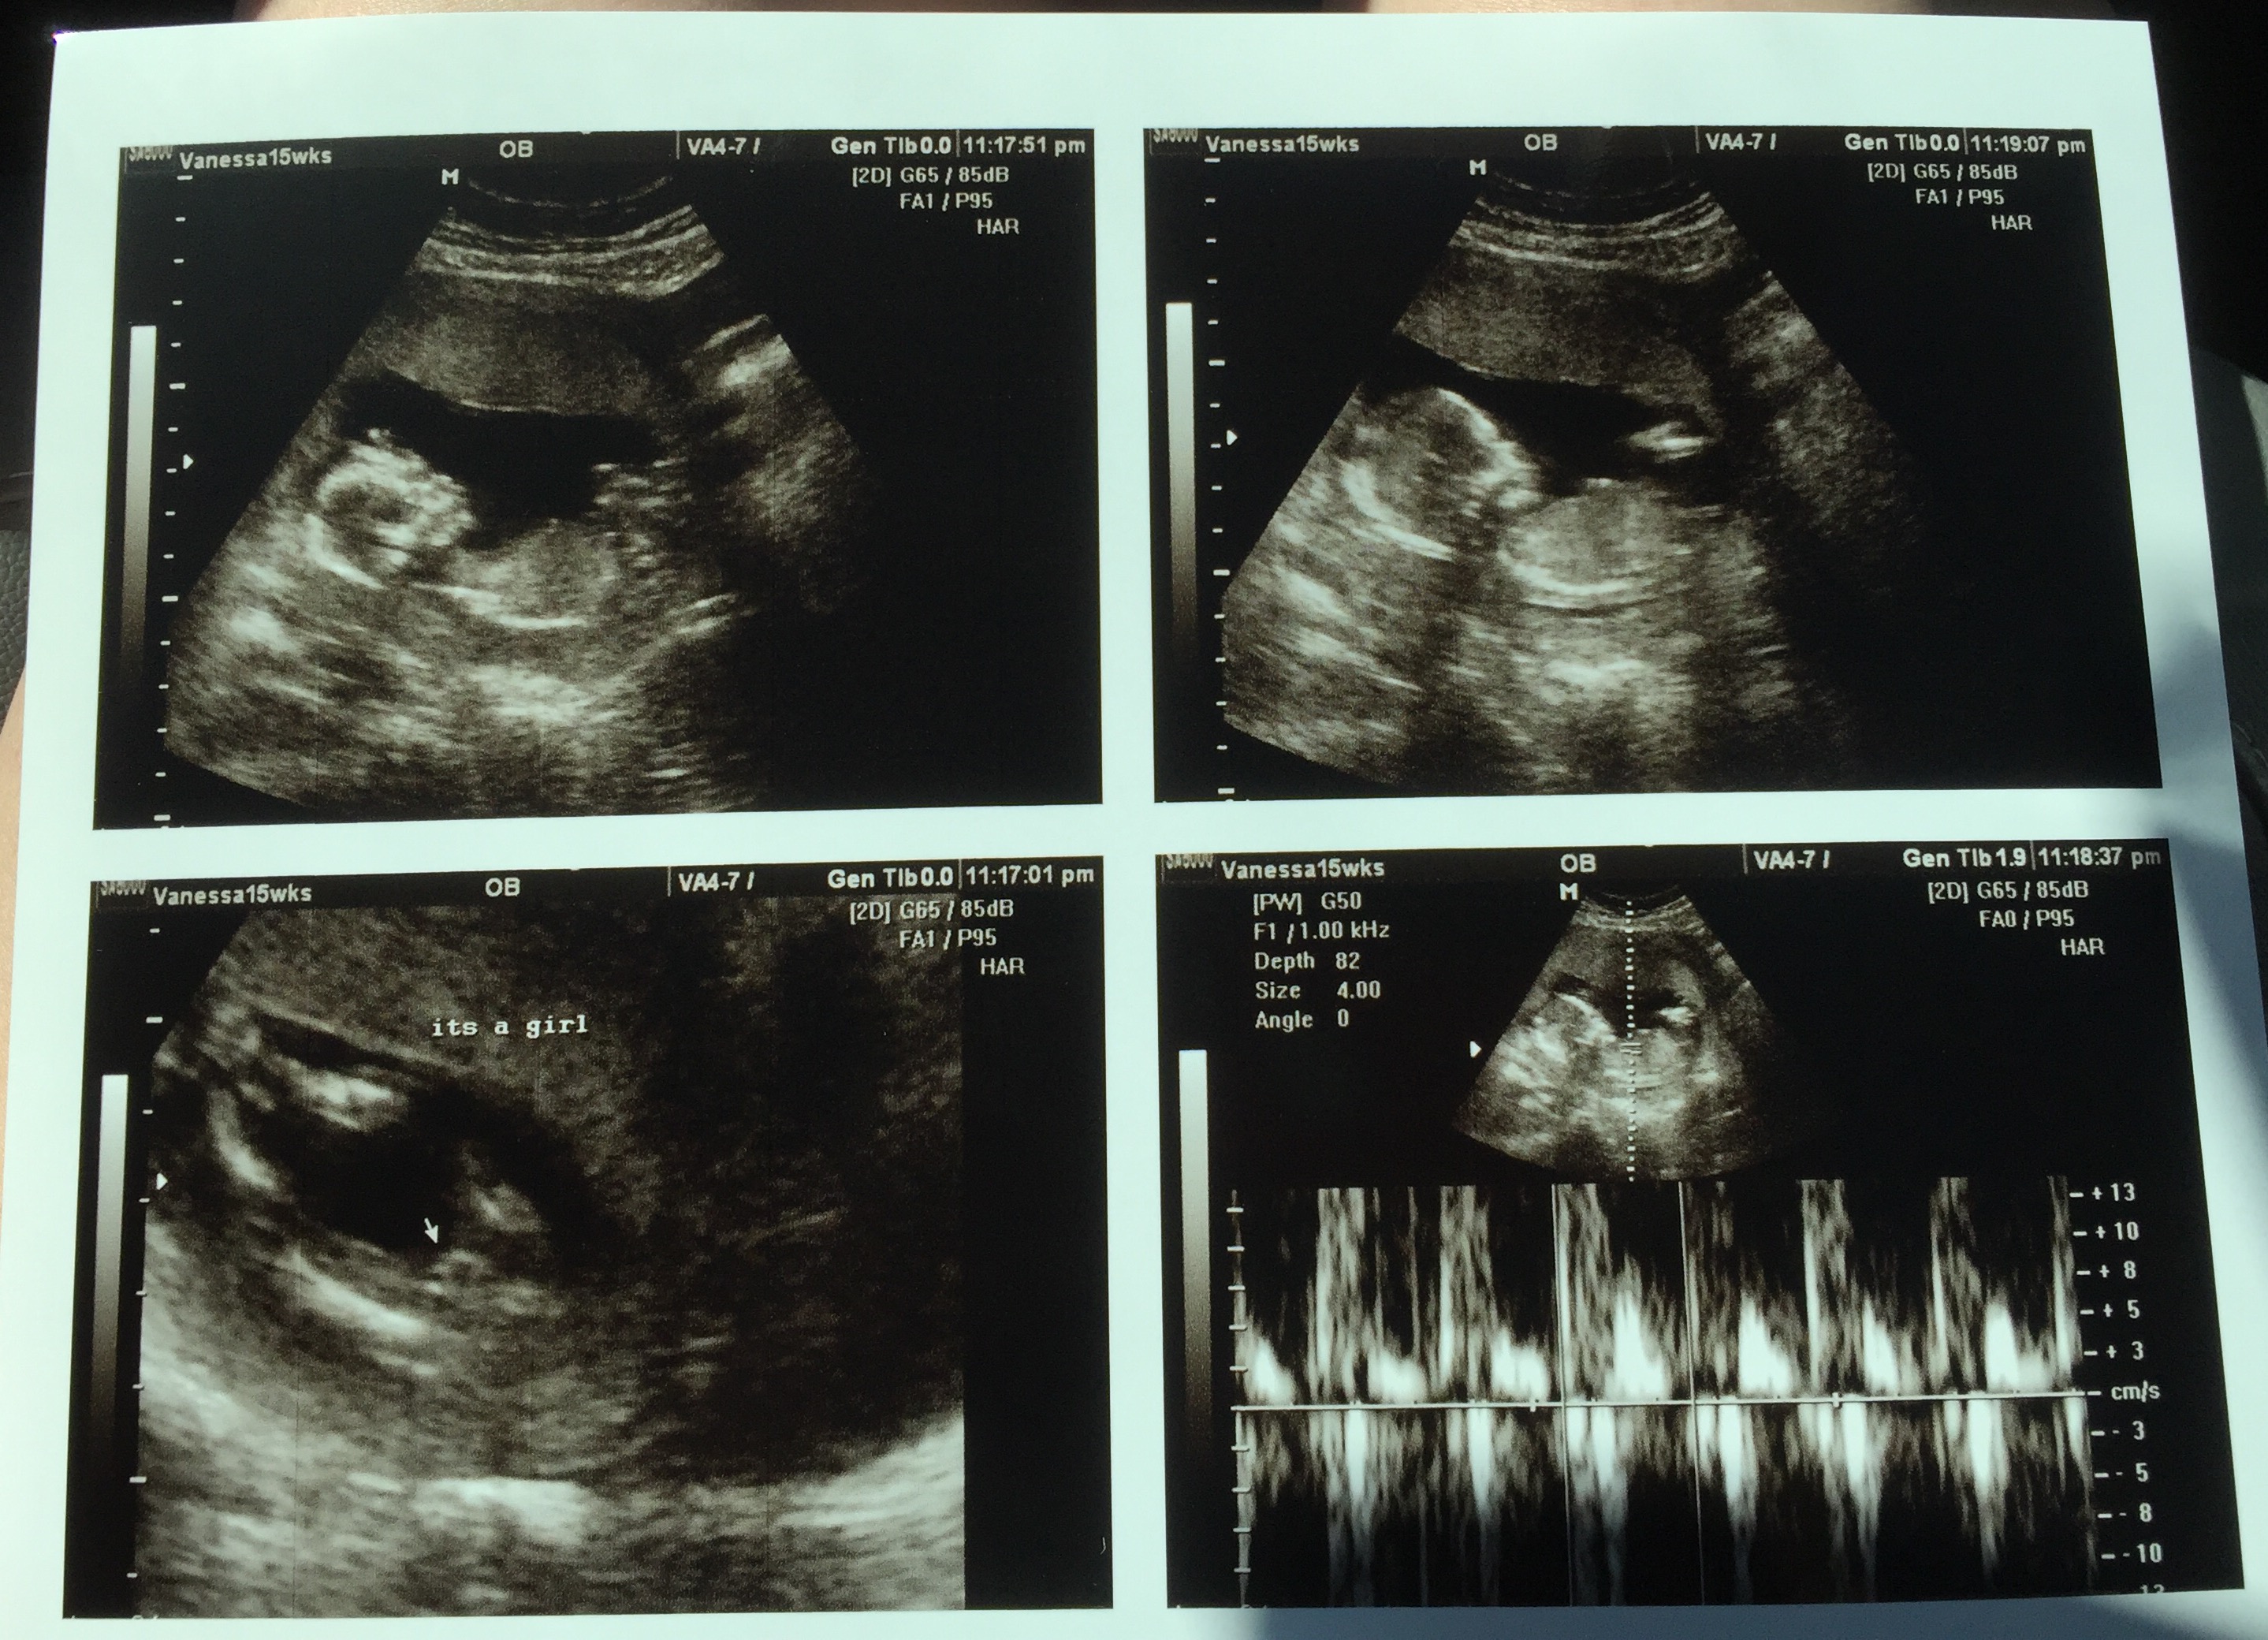

These are the best we could get because baby was VERY stubborn. Promising?Attachment 27753

It was a frustrating scan. I had to do a million jumping jacks, squats, laps around the building, etc because legs were crossed with cord in between! The tech said she suspected girl a few times during the scan but didn't say anything until she grabbed these shots.

That's exactly what the tech said lol. She said she's never had a boy be THIS modest. Ha! We got several different angles, did the blood flow numerous times to confirm cord, but never saw any boy bits trying to peak out. Unfortunately baby was in the worst position EVER and I was hoping for a nub, but she (I'm so reluctant to type that out) was being a stinker. Baby was laying upside down, diagonal with its butt crammed into the top corner of my uterus.

Looks like a girl!! 4 sons here too. I found out genders of my boys at 15 weeks and their had long noticeable pee pees around this time.